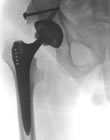

Endoprothetik

Endoprothesen sind künstliche Gelenke, mit denen ein abgenutztes oder unfallbedingt geschädigtes Gelenk ersetzt werden kann. Am häufigsten implantiert werden von uns Endoprothesen des Hüftgelenkes, gefolgt von Kniegelenk- und Schulterendoprothesen.

Endoprothesen bestehen in der Regel aus gut körperverträglichem Metall (meist Titan) und einem Spezialkunststoff. Die Metall-Kunststoff-Kombination hat einen sehr geringen Reibungskoeffizienten und ist sozusagen „selbstschmierend“.

Durch ein spezielles Oberflächendesign und genaue Einpassung können zementfreie Endoprothesen in der Regel ohne zusätzliche Hilfsmittel im Knochen verankert werden. Die endgültige Festigkeit entsteht dann durch knöcherne Umbauvorgänge nach der Operation. Der Knochen „verwächst“ mit der Prothese.

Mit der Verwendung von Knochenzement ist von Anfang an eine vollständig belastungsstabile Verankerung der Endoprothese möglich. Dafür hat Knochenzement den Nachteil, dass selten Unverträglichkeitsreaktionen möglich sind und dass die Haltbarkeit gegenüber zementfrei verankerten Endoprothesen in der Regel etwas geringer ist.